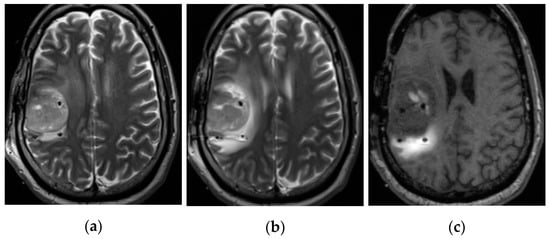

2.2.2. Imaging Protocols

2.2.3. Concentration Measurement

2.2.4. Distribution Volume Measurement